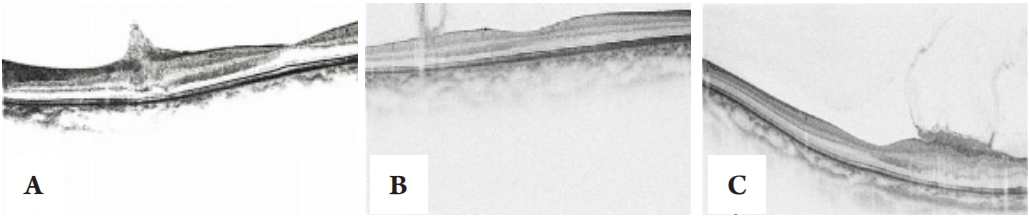

2.3 神经系统表现

3例患者患有颅内多发神经系统肿瘤,其中1例存在明显头痛。这3例患者均存在双侧桥小脑角区占位性病变,呈T1低信号,T2高信号,增强扫描明显强化且与听神经相连,其中2例患者内听道见明显扩大(图2),同时这3例患者还存在海绵窦区占位性病变,其中有1例眼球运动受限。1例延髓区及周围可见多发小类圆形明显强化小结节影,右侧枕部皮下可见不规则肿块,呈略长T1长T2信号,边界清晰,内见分隔,增强扫描肿块呈明显不均匀化。1例颈后部等T1,稍长T2信号,不均匀异常强化,舌下偏前部信号欠匀伴不规则稍长T2信号影。1例患者右侧视神经球后段局部增粗,视力在1个月内急剧下降,中心视野缺损,行γ刀治疗8个月后,右侧听神经瘤囊变体积稍大,其余肿瘤无较大变化。

图2 眼眶及颅脑MRI

Figure 2 MRI images of the orbit and brain